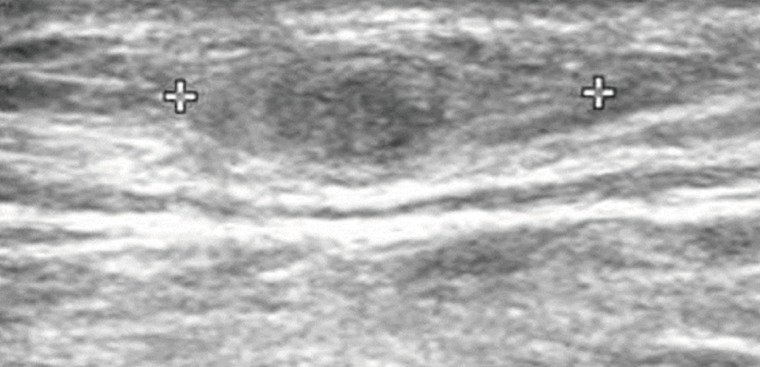

Sixteen months after the operation, the patient revisited our hospital because of pain and paresthesia of the right thigh and a mass at the posterior aspect of the right distal thigh. Physical examination revealed generalized pain and a tingling sensation on the right thigh and multiple soft, mobile, non-tender masses at the posterior aspect of the right proximal tibia. MRI revealed a 1.8 cm-sized, well-circumscribed round mass arising at the right distal sciatic nerve. The lesion showed heterogeneous high signal intensity on T2-weighted images and intermediate signal intensity on T1-weighted images with a target sign or a fascicular sign, and a benign neurogenic tumor, such as a schwannoma or neurofibroma, was suspected (Fig. 4). Multifocal tubular and cystic lesions were also detected around the mass, showing high signal intensity on T2-weighted images and low signal intensity on T1-weighted images (Fig. 5).

Fig. 4

MRI showing a 1.8 cm-sized, well-circumscribed, round mass arising at the right distal sciatic nerve. The lesion showed heterogeneous high signal intensity on T2-weighted images (arrows) (A, B) and intermediate signal intensity on T1-weighted images (arrows) (C, D) with a target sign or a fascicular sign.

Fig. 4 MRI showing a 1.8 cm-sized, well-circumscribed, round mass arising at the right distal sciatic nerve. The lesion showed heterogeneous high signal intensity on T2-weighted images (arrows) (A, B) and intermediate signal intensity on T1-weighted images (arrows) (C, D) with a target sign or a fascicular sign.